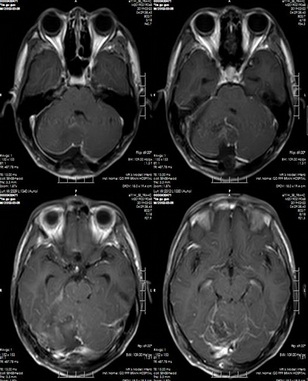

术后MR示:1.右侧小脑半球毛粘液性星形细胞瘤切除术后改变,原右侧小脑半球病变已切除;2.四脑室受压较前缓解,幕上脑室系统扩张较前缓解,脑室旁间质水肿范围较前缩小。